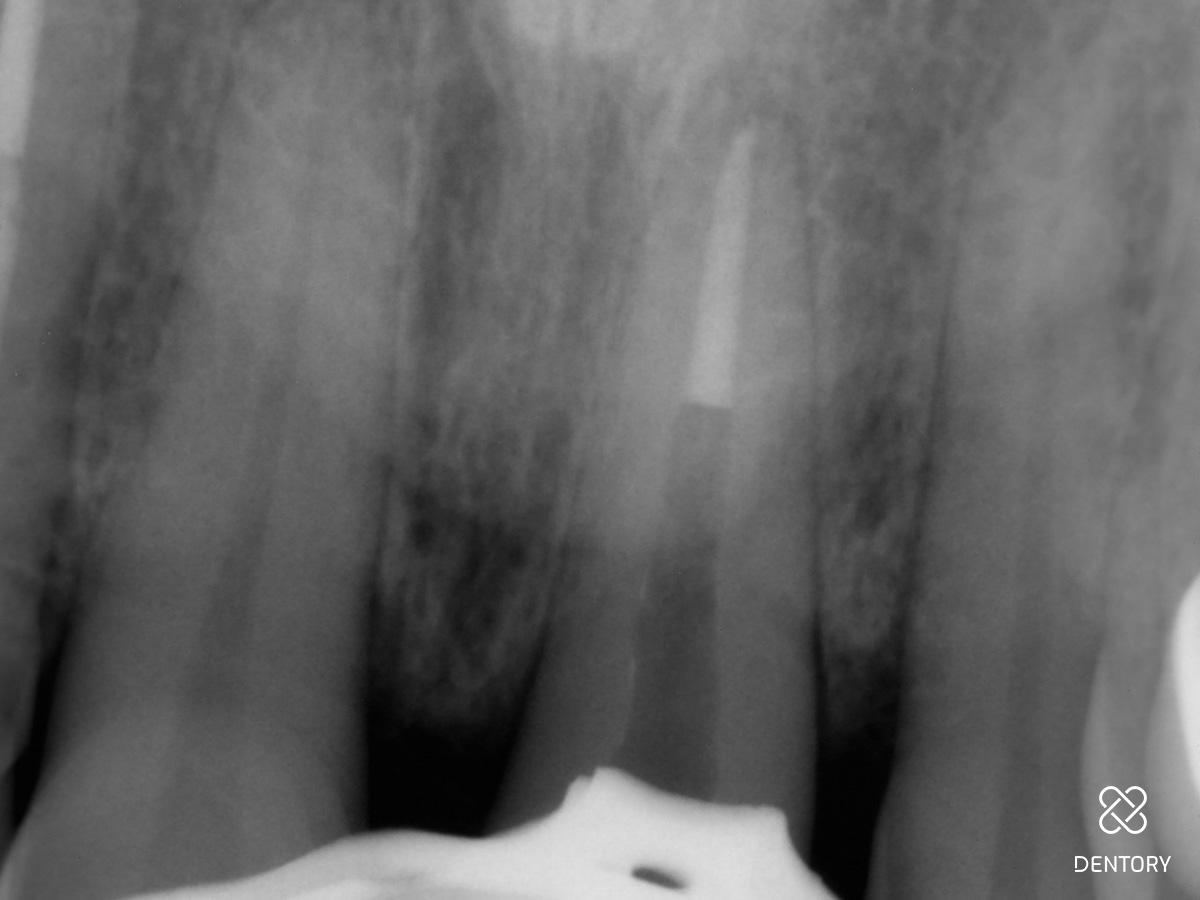

Abbildung 5

Sobald der Glasfaserstift komplett entfernt worden ist, kann mit einer Revisionsfeile weitergearbeitet werden; Sicherheitslänge: 21 mm.